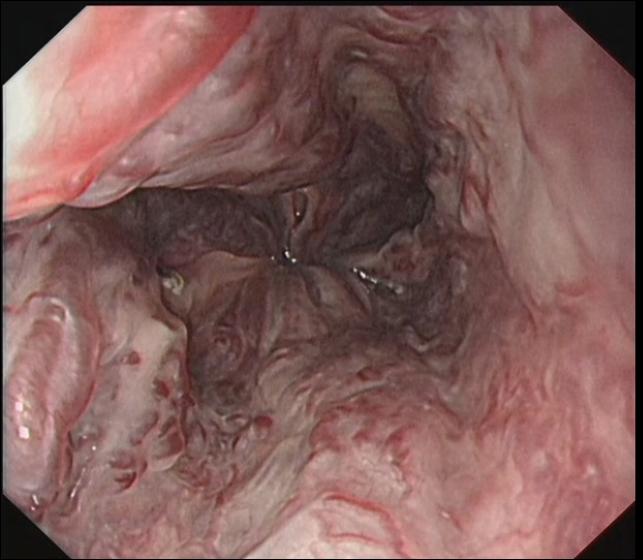

正常胃底 胃底静脉曲张TIPS术前 胃底静脉曲张TIPS术后2年

科室开展消化道早癌诊断技术、高难度食管异物取出技术、食管胃镜静脉曲张内镜下治疗、内镜逆行胰胆管造影术(ERCP术)、消化道息肉切除术、胆胰管狭窄扩张及支架植入术、内痔治疗等。

食管胃底静脉曲张破裂出血 内镜下曲张静脉结扎术后EVL